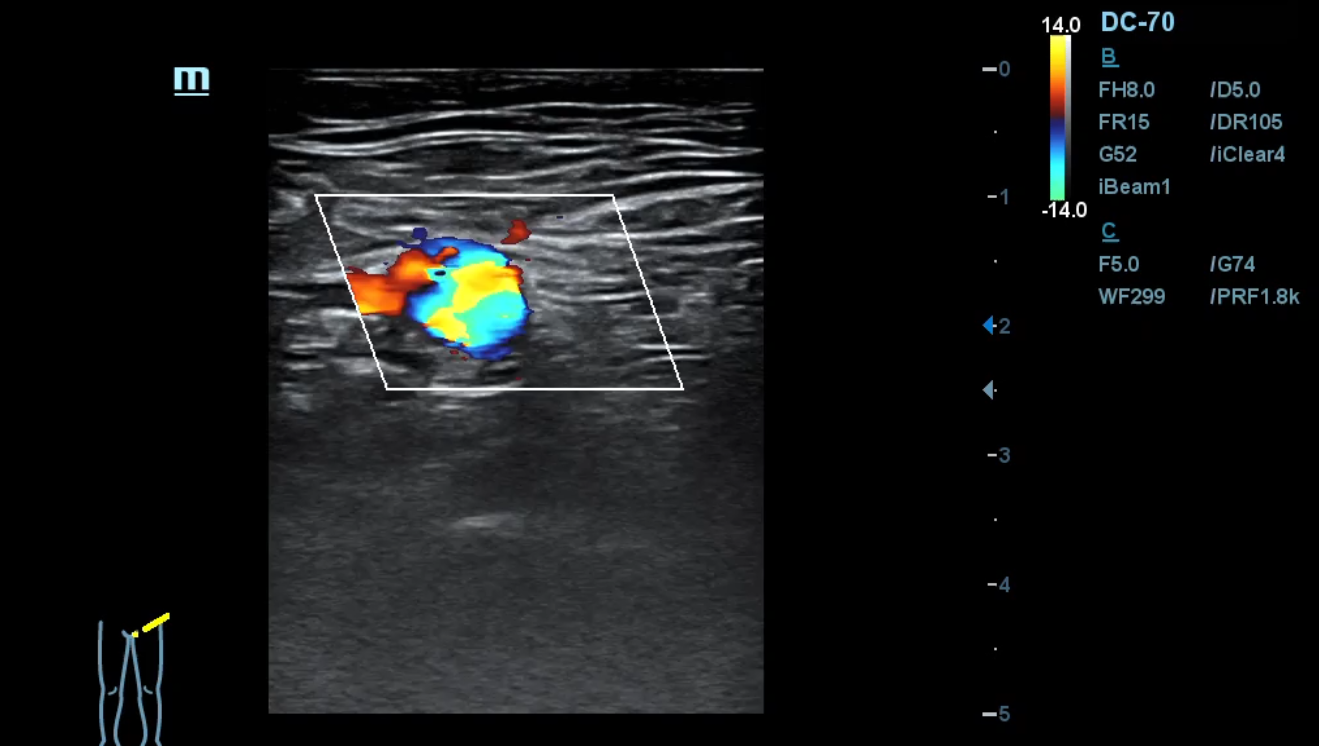

Ante los antecedentes patológicos de nuestro paciente, junto con los hallazgos relevantes de la anamnesis y exploración física decidimos realizar una ecografía clínica de miembros inferiores. En la arteria femoral común el flujo está presente. En la arteria femoral superficial se observa una obstrucción total. Así mismo, en un corte longitudinal de la arteria poplítea y tibial observamos una obstrucción total.